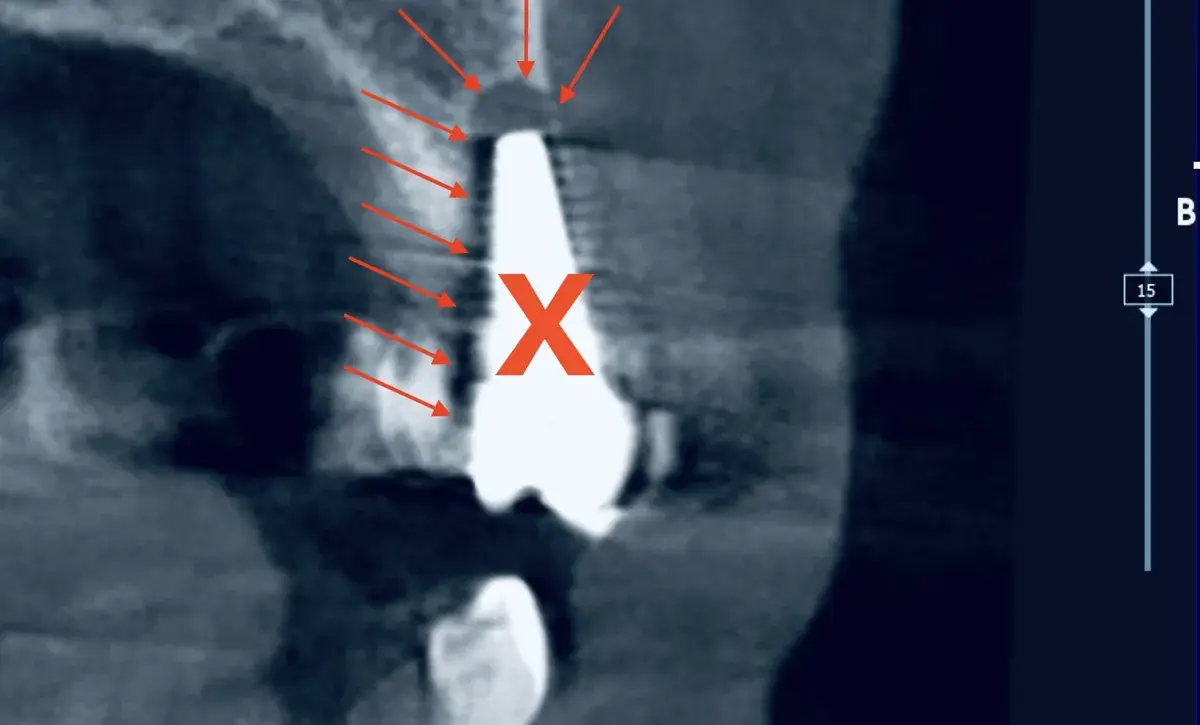

Un impianto mal posizionato causa perdita ossea di 0,25 mm ogni 10° di errore. Come riconoscere il problema, quando si può correggere e quando va rimosso.